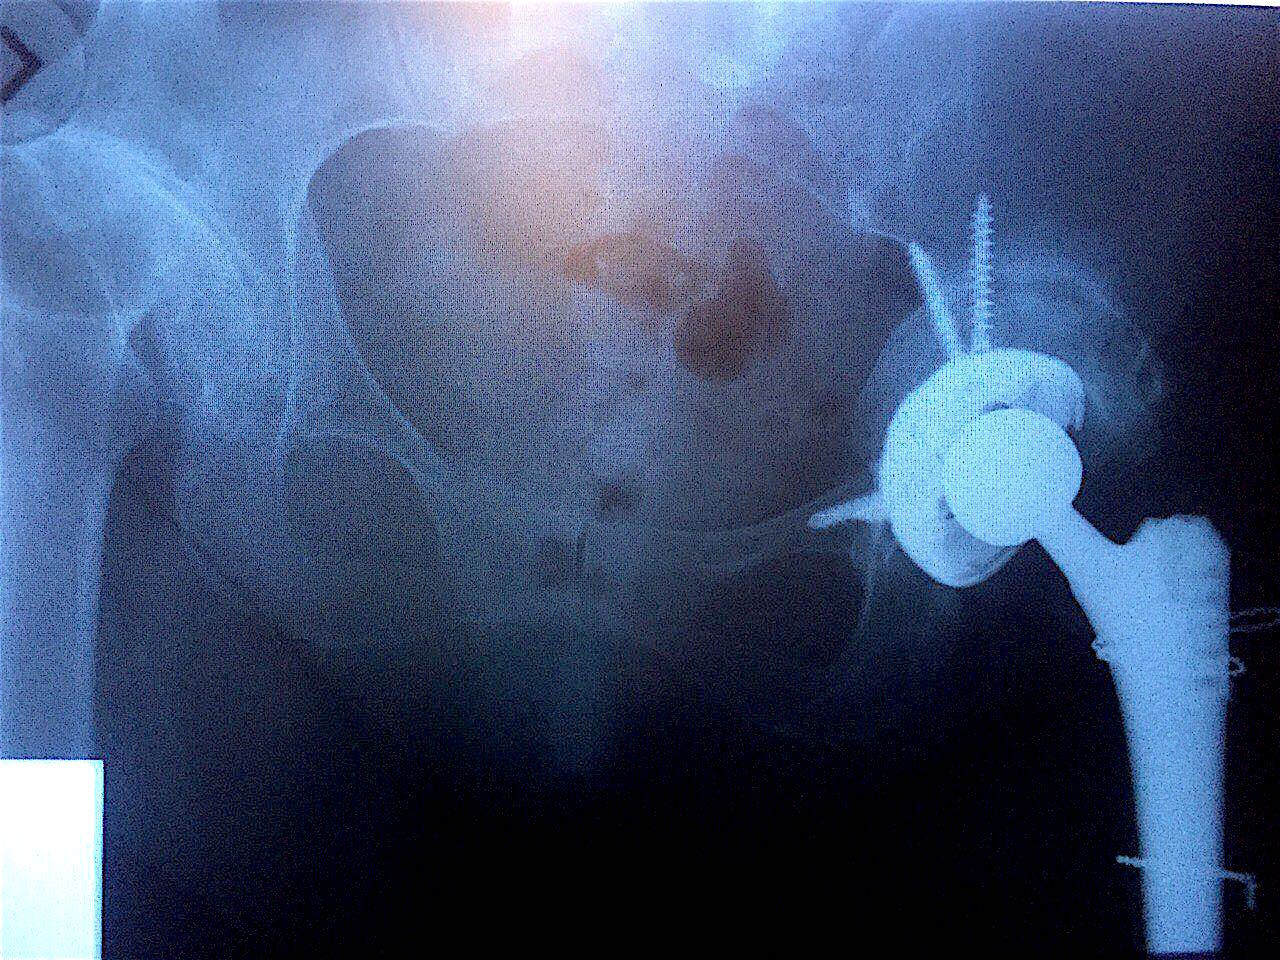

Результат через 7 месяцев после операций